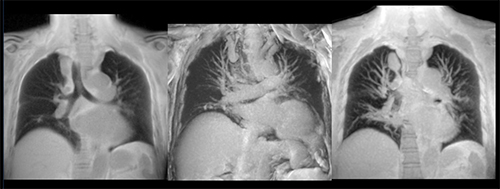

施設のニーズは日々多様化するばかりでなく,より高度になりつつある。cS Editionでは,それらの高度な新しいニーズお応えるために,多くのアプリケーションを新たに搭載した。その一つとして,放射線被ばくのないMRIでの肺野検査適応の期待に対応すべくUTE(Ultra short TE)を搭載(図4)。UTEは極めて短いT2*値の組織を画像化する手法で,従来のMRI検査では描出できなかった情報を得られると評価されている。既にUTEを先行搭載している同社3テスラ装置では,多数のサイトより,体幹部のMRI臨床応用が広がっているとの報告がある。

図4